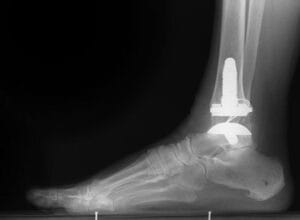

Total ankle replacement (arthroplasty). In total ankle replacement, your doctor removes the damaged cartilage and bone, and then positions new metal or plastic joint surfaces to restore the function of the joint. Although total ankle replacement is not as common as total hip or total knee replacement, advances in implant design have made it a viable option for many people.

An X-ray of a total ankle replacement (arthroplasty).

Reproduced with permission from Ishikawa SN, Gause LN: Immunologic rheumatic disorders of the foot and ankle. Orthopaedic Knowledge Online Journal 2012;Volume 10 Number 8. Accessed February 2015.